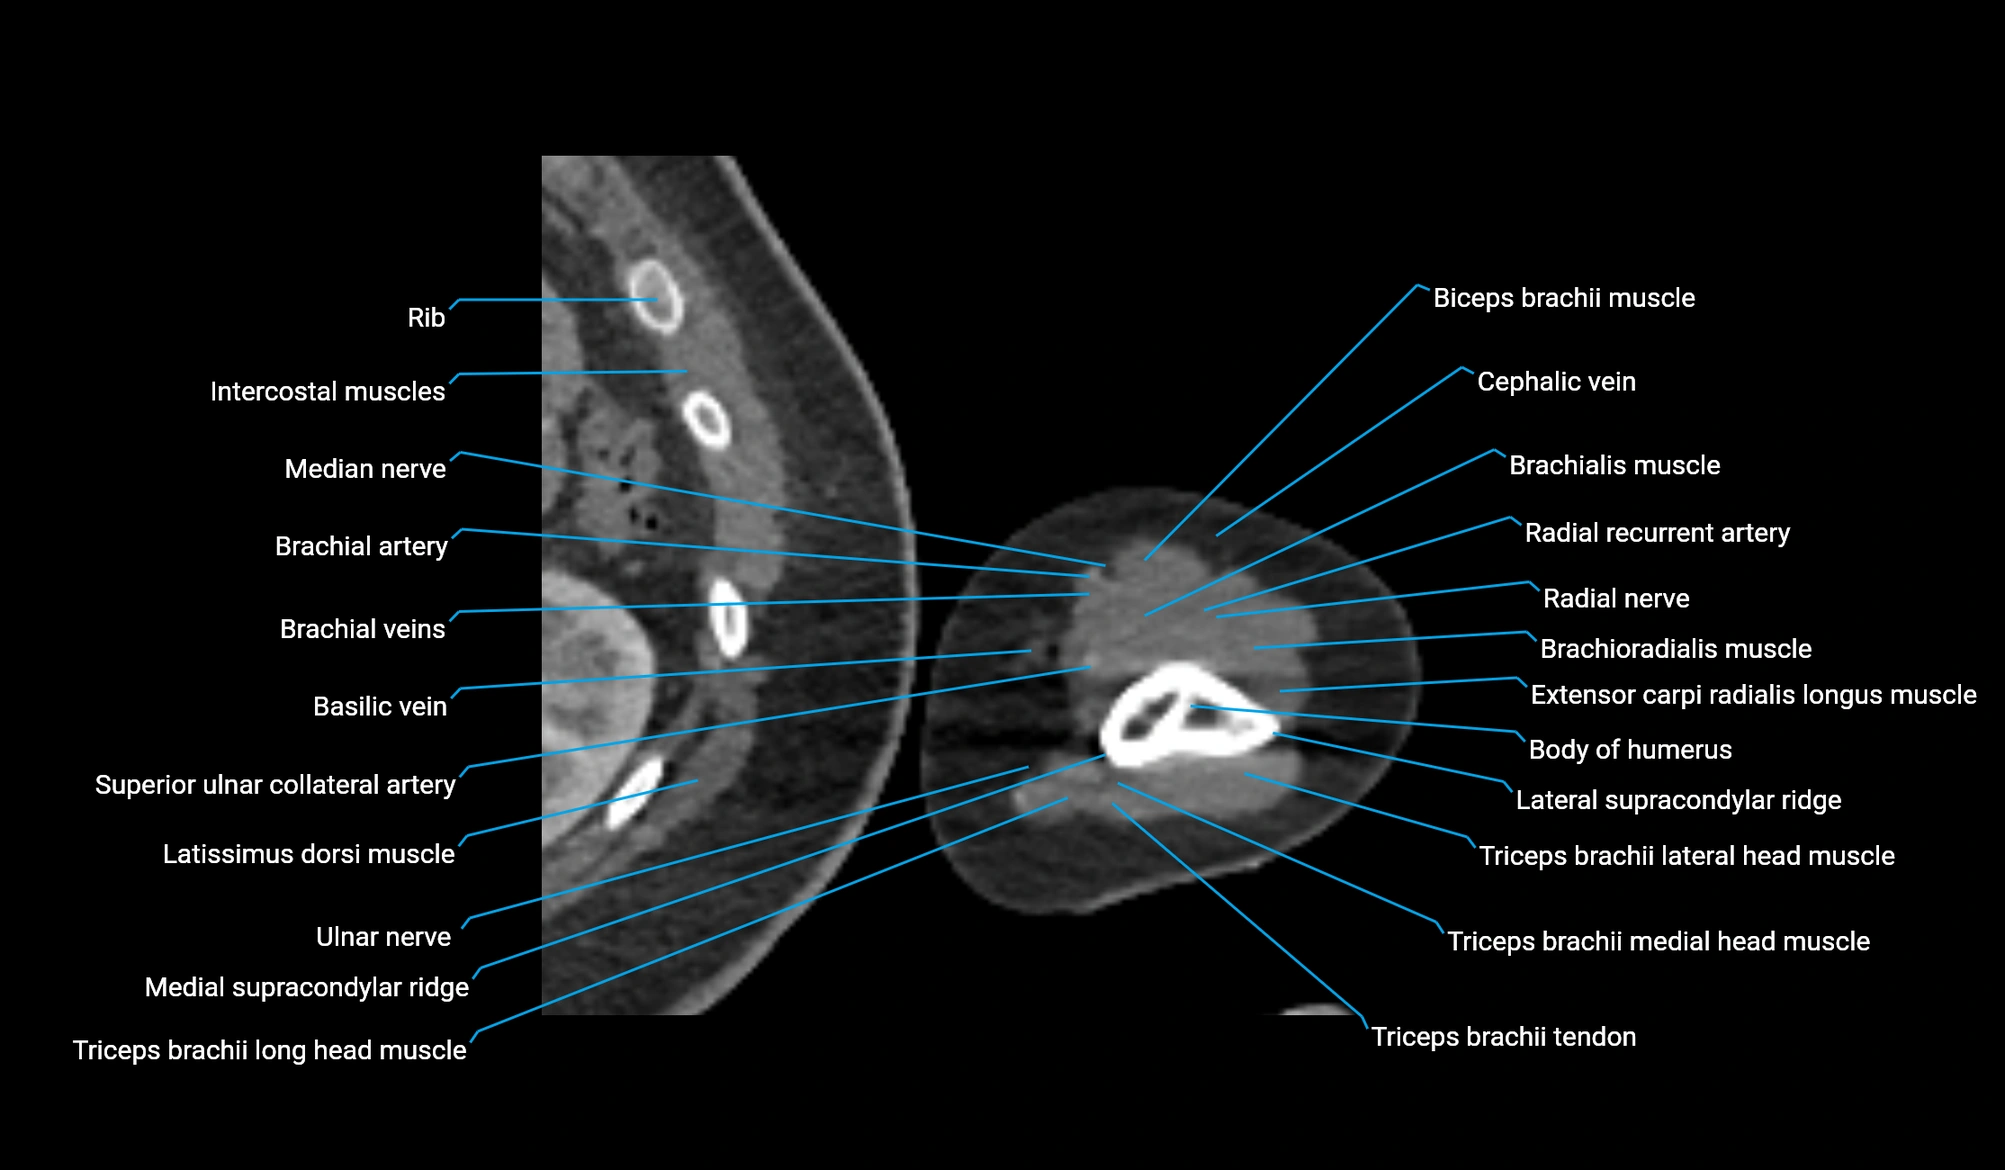

- Body of humerus

- Brachialis muscle

- Brachioradialis muscle

- Cephalic vein

- Extensor carpi radialis longus muscle

- Lateral head of triceps brachii muscle

- Lateral supracondylar ridge

- Long head of triceps brachii muscle

- Medial supracondylar ridge

- Radial nerve

- Radial recurrent artery

- Superior ulnar collateral artery

- Triceps brachii muscle

- Triceps brachii tendon